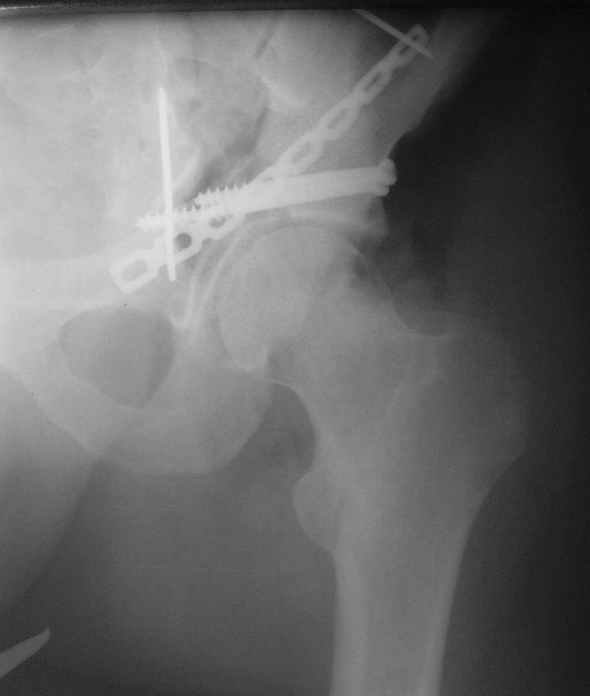

Диагноз- перелом с вовлечением таза, разрыв правого сакро-илиак сочленения vertical shear injury, перелом крыла подвздошной кости?, перелом ацетабулум Т type или Both column?, перелом шейки бедра, перелом проксимального отдела бедра.

перелом крыла правой подвздошной кости, перелом обеих колонн вертлужной впадины, двусторонний перелом лонных костей (С2.2) повреждение передних связок правого крестцово-подвздошного сочленения,

ипсилатеральный перелом шейки и диафиза бедра.

шейку (благо перелом шейки 2 типа -относительно стабильный) затем фрагмент крыла подвздошной кости Lag screw, далее пластина на заднюю колонну и винты в переднюю колонну.(с размерами и направлением винтов ошибка вышла:-((, но интраоперационно у меня была полная уверенность , что винты *ушли* в лонную кость).